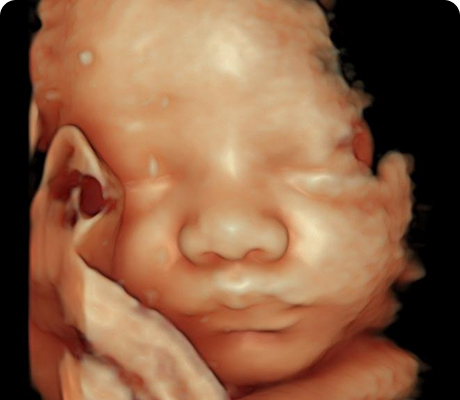

En la Clínica de Medicina Materno Fetal del Hospital Angeles Lomas, ofrecemos detección oportuna de enfermedades en el feto y complicaciones en la madre, mediante estudios de genética e imagen con tecnología avanzada y médicos altamente especializados.

"Durante el embarazo, los ultrasonidos son una parte fundamental del control prenatal. Nos permiten observar el desarrollo del bebé, identificar posibles complicaciones a tiempo y tomar decisiones médicas informadas para cuidar tu salud y la de tu bebé."